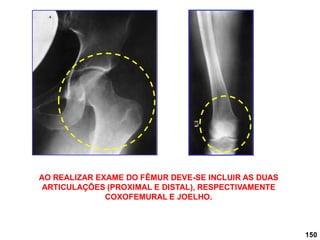

Fêmur

• AP;

• LATERAL.

DFoFi: 1 metro

No AP girar a perna

internamente 5 ou

para a porção

proximal do quadril de

10 -15 .

RC: perpendicular ao fêmur.

45

NÃO REALIZAR PERFIL EM

PACIENTE COM TRAUMA.

Básicas:

150

AO REALIZAR EXAME DO FÊMUR DEVE-SE INCLUIR AS DUAS

ARTICULAÇÕES (PROXIMAL E DISTAL), RESPECTIVAMENTE

COXOFEMURAL E JOELHO.

151